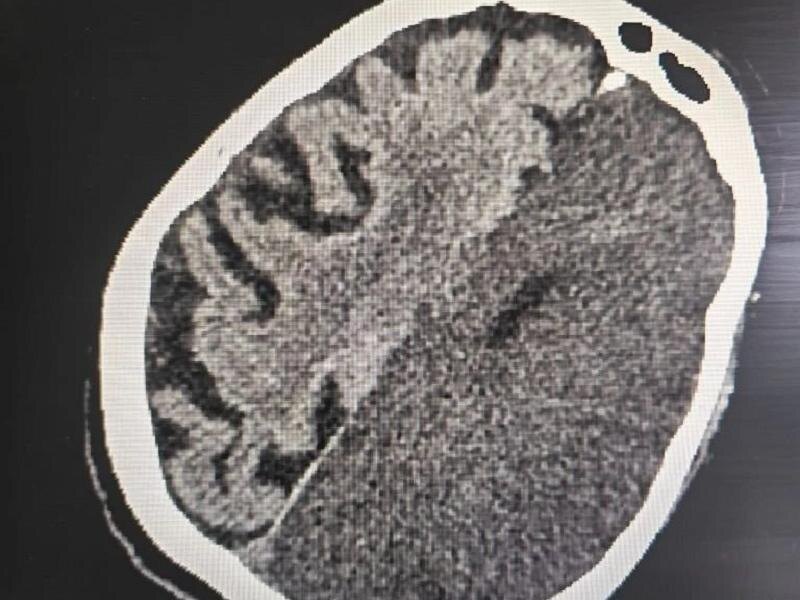

Компьютерная томография показала обширный ишемический инсульт, при котором произошло острое нарушение кровообращения и гибель клеток головного мозга – жизнь местной жительницы висела на волоске.